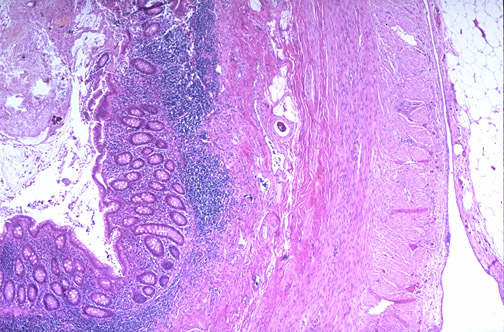

1. Mucosa

- Epithelium: Simple columnar epithelium with goblet cells lines the crypts (fewer goblet cells than colon). The surface has mucosal folds and an irregular, star-shaped lumen (especially in cross-section).

- Crypts of Lieberkühn: Present but short and irregular. Less well-developed than in the colon due to distortion by lymphoid tissue.

- Lamina Propria: Massively infiltrated by lymphoid tissue — large lymphoid follicles with germinal centres are a hallmark of the appendix.

2. Submucosa

Lymphoid Follicles: The most characteristic feature — large, well-developed lymphoid follicles with prominent germinal centres extend from the mucosa through the muscularis mucosae into the submucosa, virtually obliterating the boundary between these layers. This submucosal lymphoid infiltration distinguishes the appendix from all other GI segments.

3. Muscularis Externa

Complete inner circular and outer longitudinal smooth muscle layers (unlike the colon which has taeniae coli). Auerbach's plexus lies between the layers.

4. Serosa

Complete peritoneal covering (serosa) with a mesoappendix.

Distinguishing Features on Slide (vs. Large Intestine)

- Smaller, irregular, star-shaped lumen (colon has a larger, round lumen)

- Massive lymphoid infiltration spanning mucosa and submucosa — most distinctive feature

- Lymphoid follicles with germinal centres prominent throughout wall

- Complete muscularis externa (no taeniae coli)

- Shorter, less regular crypts than colon

- Smaller overall diameter compared to colon sections